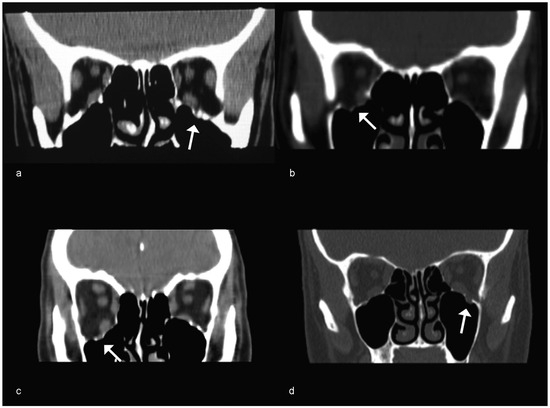

Case 5